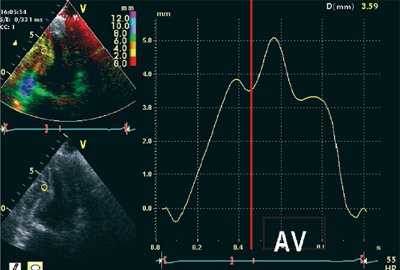

На рис. 1-5 представлены примеры проведения количественного анализа SQ (Strain quantification) тканевого допплеровского изображения в программе Q-lab 3.0. Принцип выделения изоволюмических фаз демонстрируется на рис. 1. Принцип количественного анализа деформации (ε) сегментов миокарда представлен на рис. 2-3, скорости деформации (SR) - на рис. 4, графиков SR/(ε) - на рис. 5.

![Пример определения длительности изоволюмических фаз при постобработке данных тканевого допплеровского исследования у пациента с выраженной ГЛЖ]()

Рис. 1. Пример определения длительности изоволюмических фаз при постобработке данных тканевого допплеровского исследования у пациента с выраженной ГЛЖ.